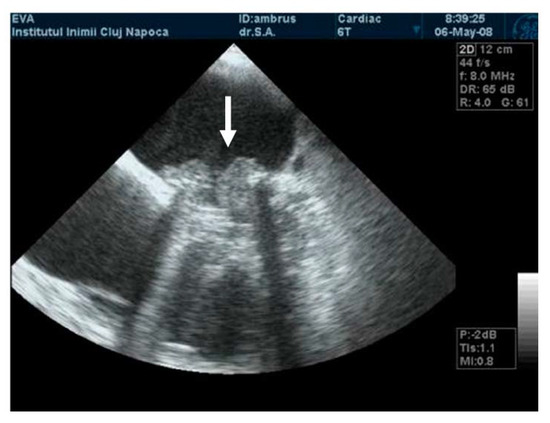

The mobility of the discs and the presence of pathological features such as thrombus, pannus, or vegetation are evaluated using bidimensional echocardiography. The thrombus can sometimes be difficult to visualize; in some cases, it appears as an echodense mass that is located on the discs and restricts their motion (Figure 2A) [17]. The colour Doppler flow quantification may reveal a turbulent flow above the valve or even the absence of colour flow through the prosthesis (Figure 2B). While 2D imaging leaves room for ambiguity in terms of thrombus localization in relation to the prosthesis, 3D images clearly reveal the relationship between them, as illustrated in the moving images of Video S1 (Supplementary Material). The evaluation of intracardiac masses suspected for thrombi using pulsed wave (PW) tissue Doppler imaging (TDI) might be an improvement over visual assessment, as it provides a more precise definition of mass mobility [18,19].

Figure 2.

(A) TTE. Prosthetic mitral valve PLAX thrombus on the disc left atrial side (arrow). (B) TTE. Colour Doppler turbulent flow above the prosthesis (arrow).